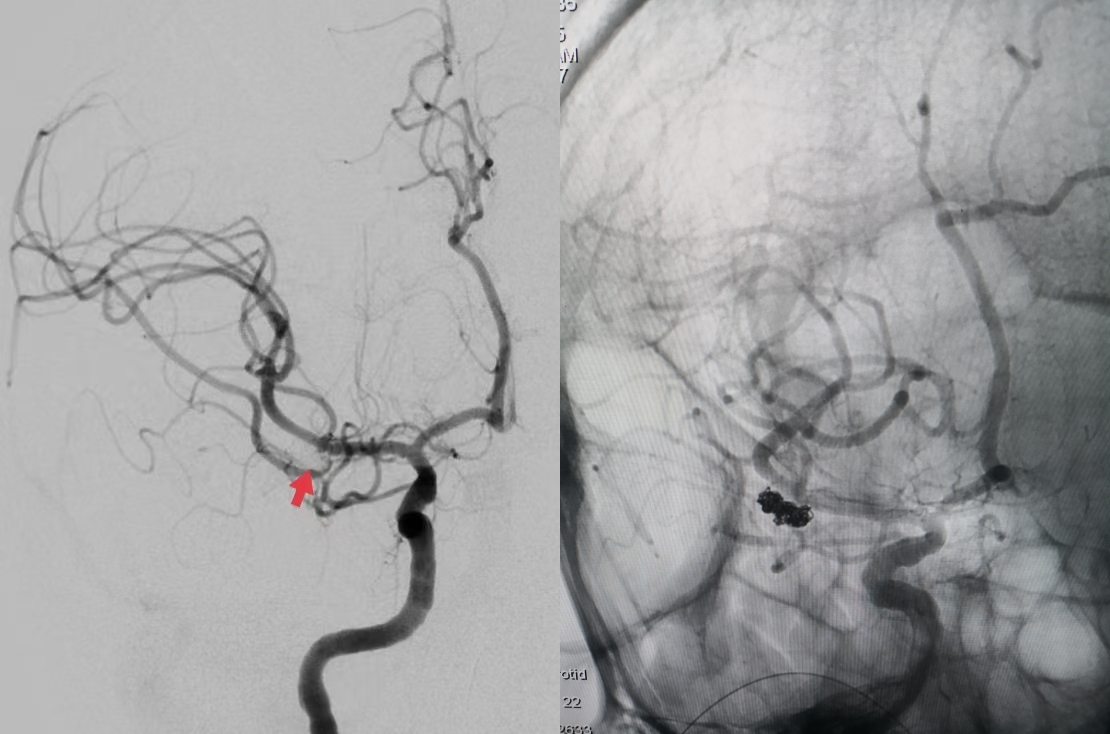

脑血管造影显示右侧大脑中动脉M1段分叉不规则动脉瘤,累及下干,角度刁钻。神经外科副主任医师刘磊决定采用单纯弹簧圈栓塞动脉瘤,避免因支架植入后需口服抗血小板药物进而影响后续的有创手术。经过2小时的手术,动脉瘤达到了致密栓塞,不定时炸弹拆除了,载瘤动脉各分支血流通畅。

脑血管造影显示右侧大脑动脉M1段分叉部不规则动脉瘤

术后即刻造影,动脉瘤致密栓塞,载瘤动脉通畅